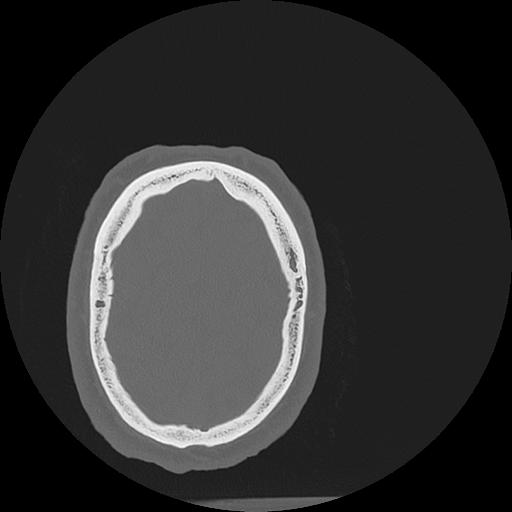

7 HUESO,,Vol,0.5,HUESO,,